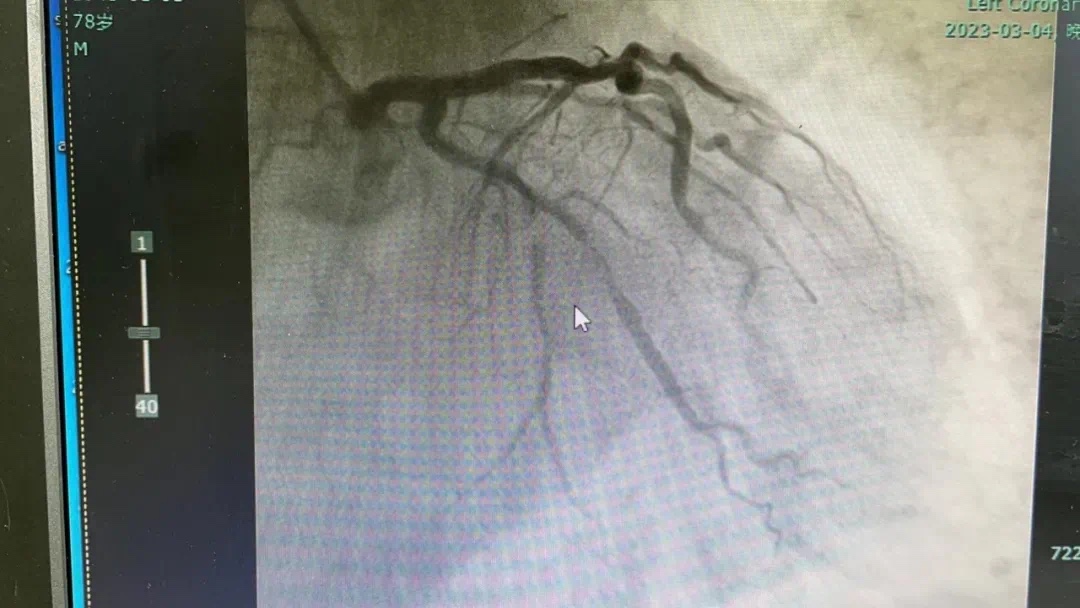

3月4号晚,总医院一个不平凡之夜。19点44分,急诊科汪小卫医生在胸痛中心微信群发送了一条信息:患者程某心电图检查结果。心内科副主任何涛马上回复:患者确诊为急性下壁ST段抬高型心肌梗塞并一键启动导管室,医生熊俊锋、导管室张梅梅立即奔赴导管室穿好铅衣备好急救药品物品,打开除颤仪做好手术准备。19点54分,激活导管室。20点08分患者被送入导管室快速实施冠脉造影,显示患者右冠近段粥样硬化伴“瘤样扩张”,中段发生完全闭塞。结合心电图考虑堵塞血管为右冠,于20点27分成功开通堵塞血管。患者从医院大门到开通血管仅50分钟,大大缩短心肌获得灌注时间,心功能基本不受影响。 术中险象环生,患者心率进行性下降,血压反复异常,经医护人员的及时救治,患者转危为安被安全护送回病房。术前、术后图片如下